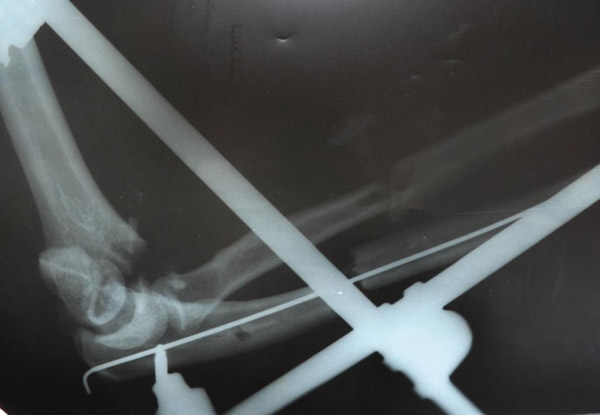

С  2009г  начали  выполнять  протезирование  тазобедренного  сустава  однополюсными  гемипротезами.  Широко  используется  накостный  остеосинтез,  интрамедулярный  остеосинтез  с  блокированием,  чрезкостный остеосинтез  (ЧКОС).

"до операции"